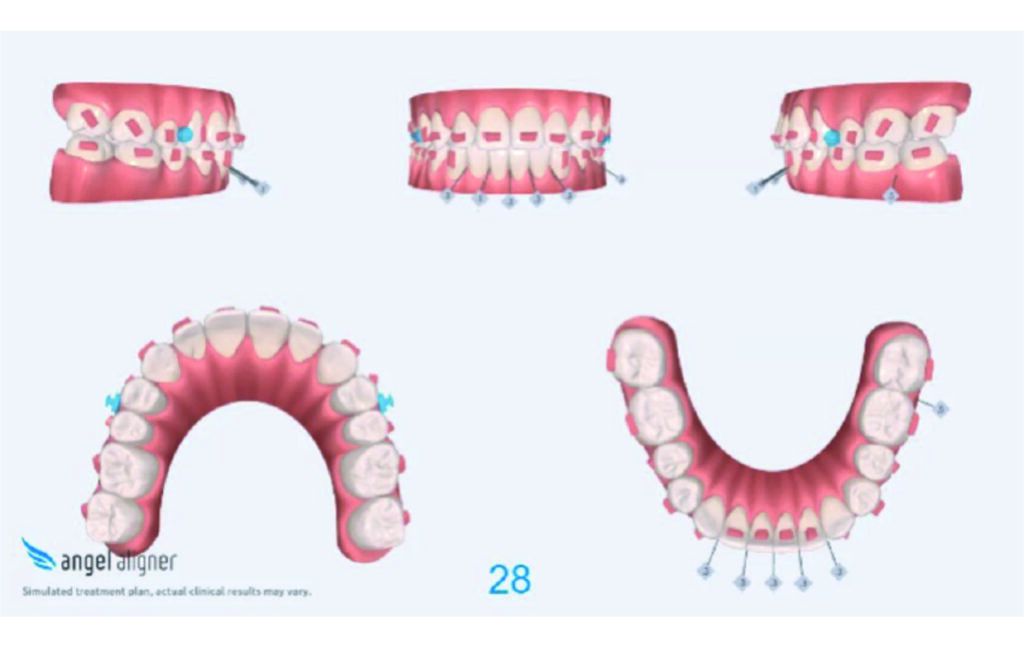

Treatment details

Derotation of 16 26 allowed Class II correction.

Vertical vector of elastic traction on buttons and IZC helped with the open bite correction.

No sequential distalization for Class II tendency correction was performed due to skeletal anchorage. Lingual attachments were used to improve aligner grip and control tooth movement, as small, angulated lower incisors are difficult to move due to limited anatomy.

An infrazygomatic crest (IZC) screw with force applied between the upper premolars produces a clockwise rotation of the maxillary occlusal plane. This movement aids in closing the anterior open bite and improves upper incisor display. IZC screws with elastics also enable planned intrusion of the upper molars by 1 mm. Because mandibular derotation after upper posterior correction is difficult to predict, anterior distalization and midline correction were performed in the later stages of treatment.

Treatment setup